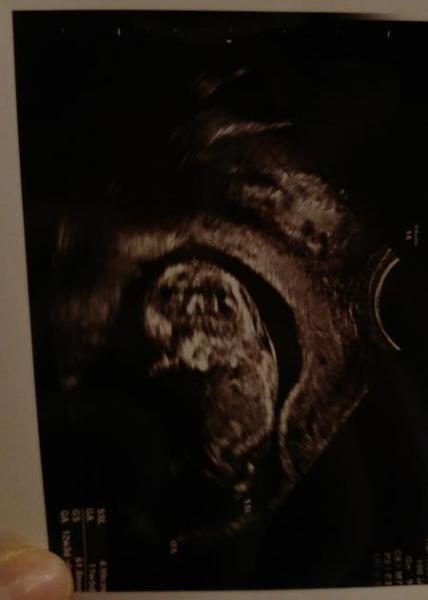

Siehe oben. So sieht mein aktuelles Hämatom aus..:/

Bild zu